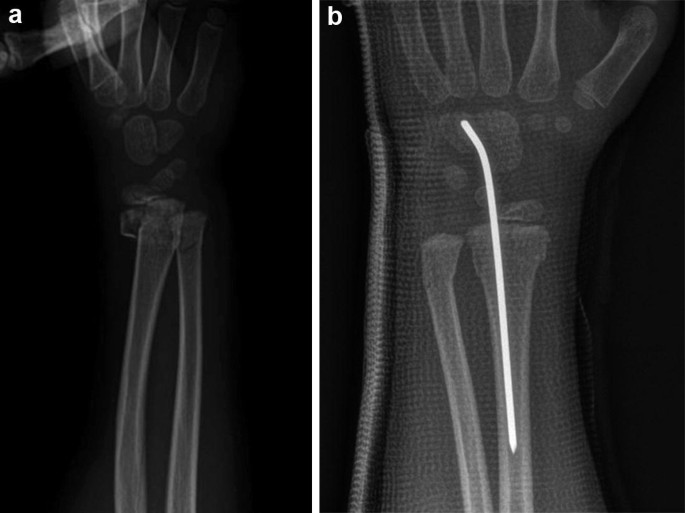

کی میتوانم مرخص شوم و چه مراقبتیهایی در طول بستری باید رعایت کنم؟ معمولاً ترخیص شما روز بعد از عمل انجام خواهد شد. در طول مدت بستری اندام شما از...

کی میتوانم مرخص شوم و چه مراقبتیهایی در طول بستری باید رعایت کنم؟ معمولاً ترخیص شما روز بعد از عمل انجام خواهد شد. در طول مدت بستری اندام شما از...